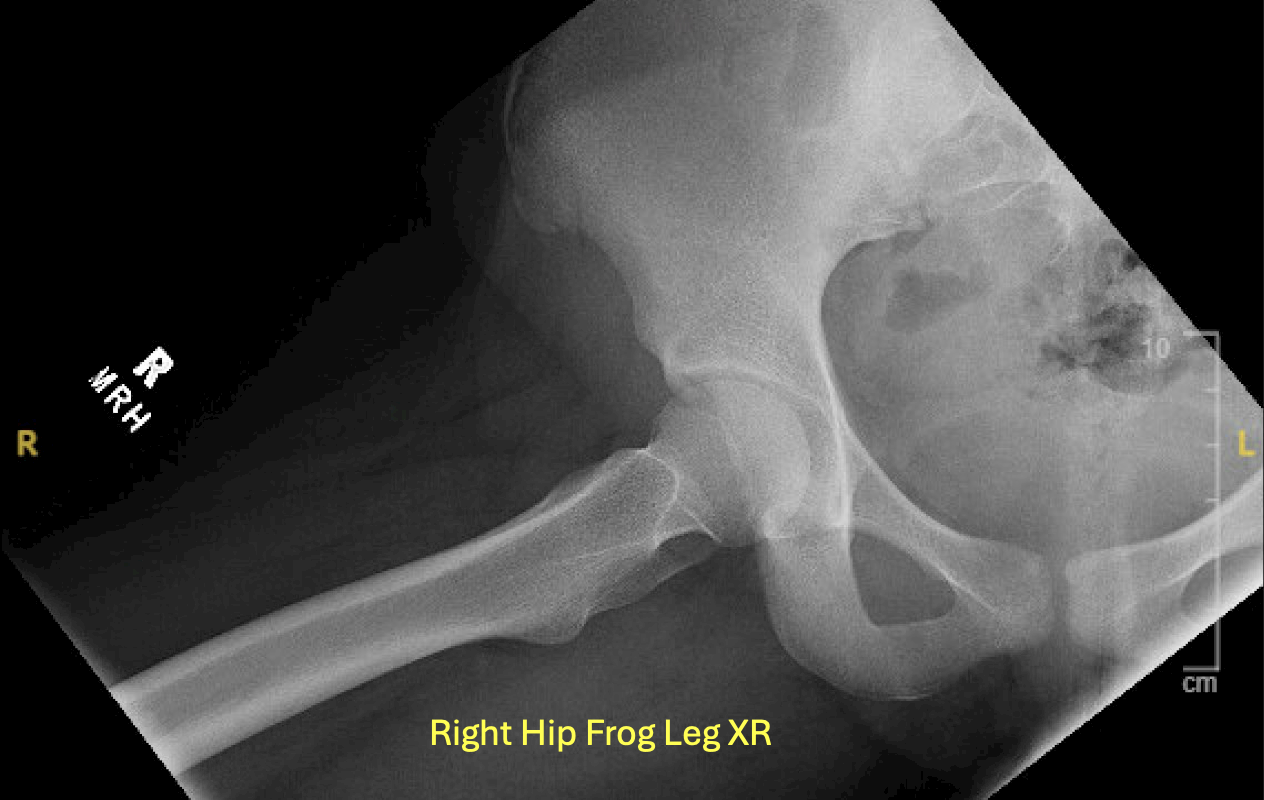

Unlabeled Frog Leg View XR correlate.

Labeled Frog Leg View XR correlate.